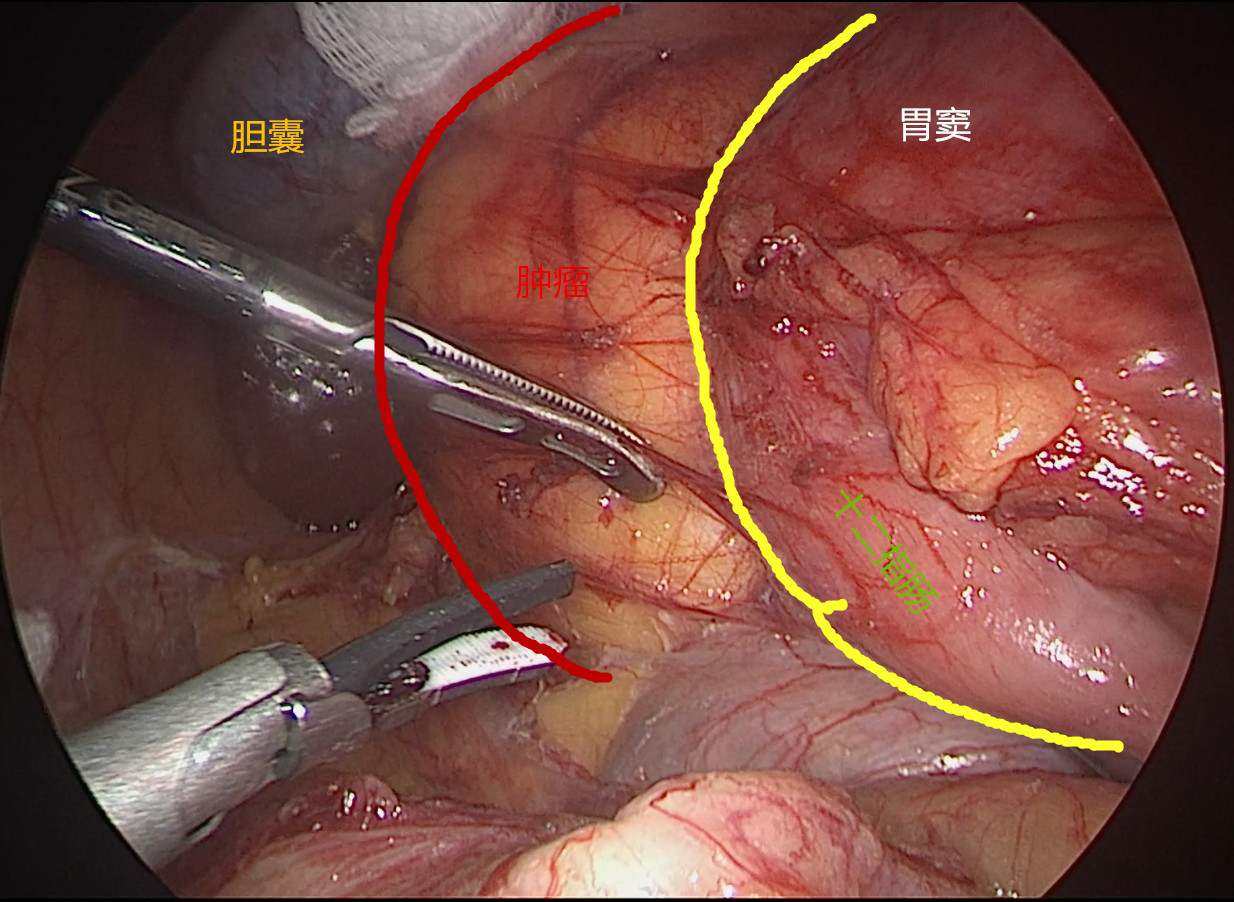

患者女性,45岁,体检发现后腹膜占位2月。CT提示:“胰腺后方可见约63*90mm混杂密度肿块影,内可见囊实性区及脂肪、牙齿,增强扫描实性区动脉期轻度强化,门脉期明显强化,边界清;腹腔干、肠系膜上动脉受压移位,考虑畸胎瘤诊断”。患者后腹膜占位诊断明确,肿瘤较大周围脏器受压,手术指征明确,拟行腹腔镜手术探查。手术困难所在:1.病变位于肝十二指肠韧带、十二指肠、胰头及横结肠后方暴露困难;2.毗邻关系复杂,病变周围与肝脏、胆囊、胆总管、横结肠、胃窦、十二指肠及胰头等重要器官毗邻;3.周围大血管多,病变与门静脉、肝总动脉、腹腔干、肠系膜动静脉、下腔静脉及左肾静脉关系密切,易导致术中大出血;4.病变系囊实性肿块牵引提拉困难。今经过团队两个小时的努力顺利切除肿瘤,术中出血约100ml。感谢麻醉师、护士及团队的辛勤付出,祝患者早日康复。